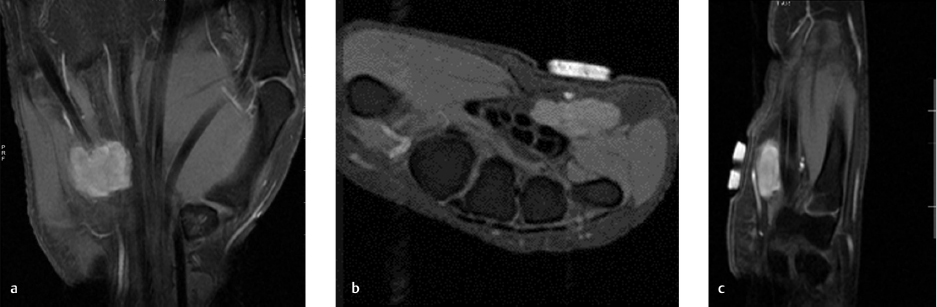

Ulnar tunnel syndrome has been well-described in the literature and might be the result of various causes, including ganglia 8 , 9 , 10 , 11 (as depicted in ► Fig. 26.4), fractures or dislocations of the ulnar side of the wrist, 9 , 12 , 13 anomalous muscle bellies or fibrous bands, 11 , 14 , 15 (as shown in ► Fig. 26.5), hemangiomas, 16 bipartite hamate, 17 giant cell tumors, 18 thrombosis of the ulnar artery, 9 , 11 , 19 osteoarthritis of the distal radioulnar joint and carpal joints, 20 , 21 rheumatoid tenosynovitis, 22 other benign soft tissue masses (shown in ► Fig. 26.6), bicycle racing, and other activities that require either prolonged wrist hyperextension or continuous pressure on the hypothenar eminence. 16 More recently, with the extreme popularity of indoor cycling classes, we have seen an increased prevalence of this condition which is termed cyclers’ palsy.